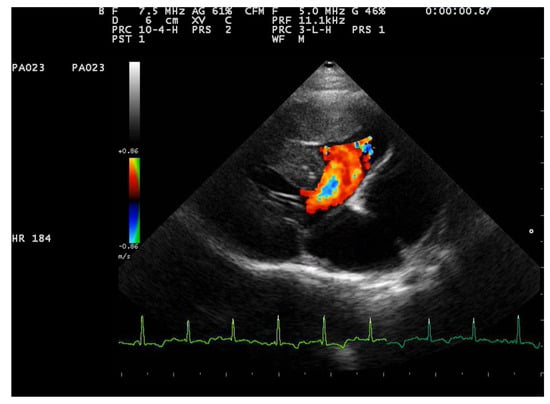

Two-dimensional echocardiography revealed significant hypertrophy of the right ventricular free wall, with a diastolic thickness of 8.7 mm, accompanied by prominent papillary muscles. The right atrium was severely dilated (maximum diastolic cranio-caudal diameter of 20.3 mm, compared to the reference value of 12 mm in healthy cats) [11]. The leaflet edges of the tricuspid valve were severely thickened. (Figure 1). The left atrium was within normal limits, with a maximum diastolic cranio-caudal diameter of 13.7 mm, compared to the reference value of 16 mm [12], while the left ventricular free wall was hypertrophic, with a diastolic thickness of 7.3 mm measured in 2D echocardiography. In the right parasternal short-axis view at the level of papillary muscles, the interventricular septum was flattened in both systole and dyastole (Figure 2). A large interventricular septal defect (VSD) was identified in both right parasternal long-axis and short-axis views, with a diameter of at least 10.2 mm measured in the long-axis view. Color-flow Doppler examination revealed a left-to-right shunt through the VSD (Figure 3), with a peak velocity of 1.3 m/s. A single large trunk was identified, originating from the base of the heart and communicating with both ventricles. Caudal vena cava was not dilated and had an inspiratory collapse.

Figure 3.

Right parasternal long axis view from a 2-year-3-month-old domestic shorthair neutered male cat. Color Doppler interrogation at the level of the ventricular sept defect identified a left-to-right flow.